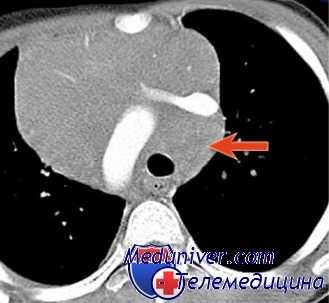

Но бывают сложные ситуации. Пациент 32-х лет, который был направлен к нам на компьютерную томографию (он ВИЧ-инфицирован несколько лет) для уточнения изменений в проекции корня левого легкого. Мы видим подозрение на патологическое образование в корне легкого: деформированы контуры.

При нативном исследовании видно, что отмечается локальное расширение аорты в области дуги. Но наряду с этим, посмотрите, выявляются увеличенные лимфатические узлы (они здесь показаны желтыми стрелками) в бифуркационной группе и трахеобронхиальной группе.

Размеры их – где-то до 1,5 сантиметров. Это пограничные размеры. Существует много дискуссий по поводу того, какие должны быть размеры лимфатических узлов.

После проведения внутривенного контрастирования мы четко видим аневризматическое локальное расширение дуги аорты.

Посмотрите, как лимфатические узлы (даже незначительно увеличенные) накапливают контрастный препарат: фрагментарно, по капсуле. Это позволило высказаться о том, что у пациента наряду с локальным расширением имеется и туберкулез внутригрудных лимфатических узлов.

Ему была назначена противотуберкулезная терапия. В динамике (мы видим здесь уже без контрастирования исследование) – уменьшение размеров лимфатических узлов и частичное обызвествление.